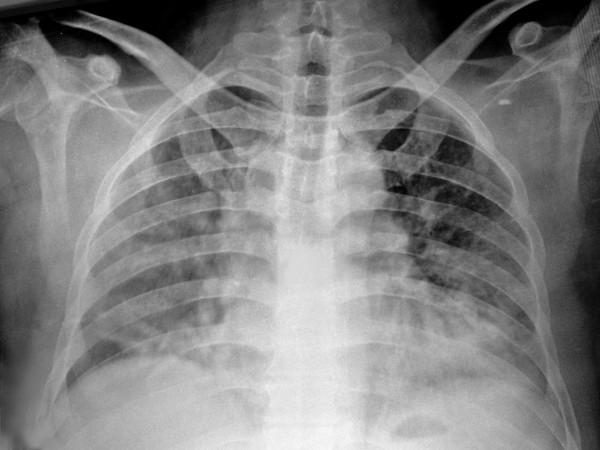

Q fever is a worldwide zoonotic infection that caused by Coxiella burnetii, a strict intracellular bacterium. It may be manifested by some of the autoimmune events and is classified into acute and chronic forms. The most frequent clinical manifestation of acute form is a self-limited febrile illness which is associated with severe headache, muscle ache, arthralgia and cough. Meningoencephalitis, thyroiditis, pericarditis, myocarditis, mesenteric lymphadenopathy, hemolytic anemia, and nephritis are rare manifestations. Here we present a case of acute Q fever together with Coombs' positive autoimmune hemolytic anemia (AIHA) and tubulointerstitial nephritis treated with chlarithromycin, steroids and hemodialysis. Clinicians should be aware of such rare manifestations of the disease.

Q 热是一种由严格细胞内菌贝氏柯克斯体引起的世界性动物源性感染。它可能表现为某些自身免疫事件,并分为急性和慢性两种形式。急性形式最常见的临床表现是一种自限性发热疾病,伴有严重头痛、肌肉疼痛、关节炎和咳嗽。脑膜脑炎、甲状腺炎、心包炎、心肌炎、肠系膜淋巴结病、溶血性贫血和肾炎是罕见的表现。在此,我们报告了一例急性 Q 热合并 Coombs 阳性自身免疫性溶血性贫血(AIHA)和肾小管间质性肾炎,采用克拉霉素、类固醇和血液透析治疗。临床医生应注意该病的这些罕见表现。